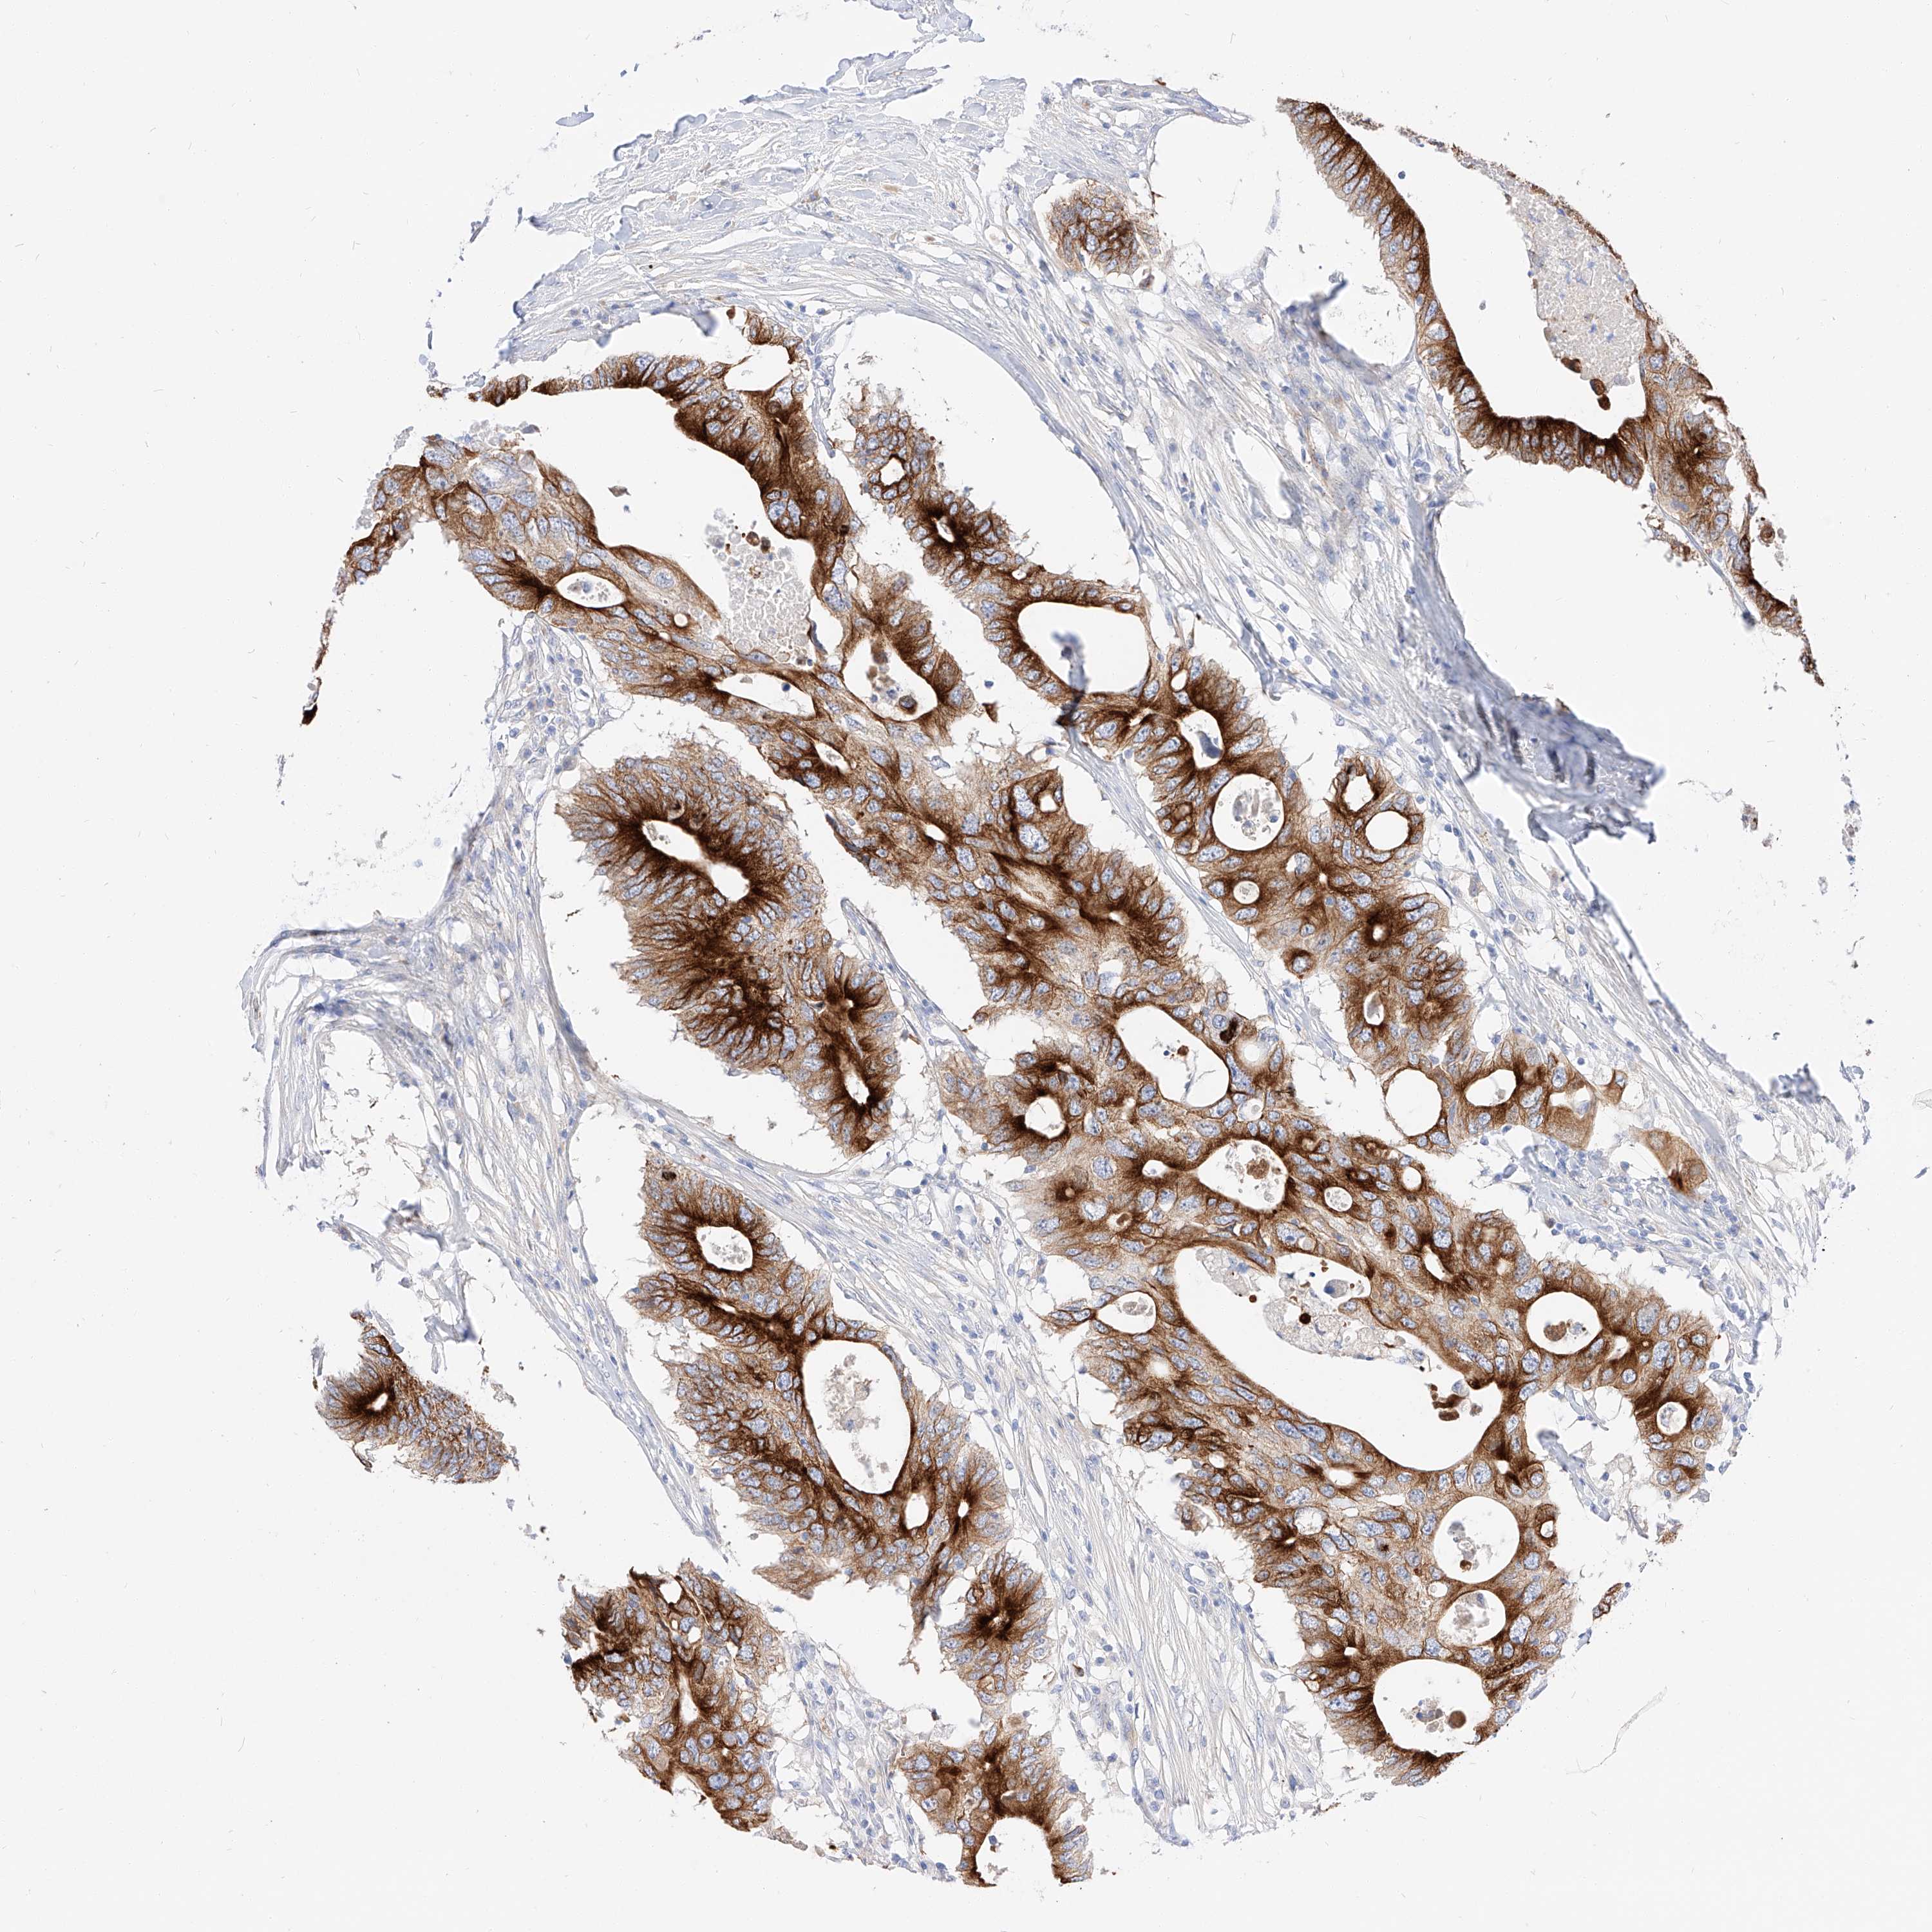

CANCER COLORECTAL CANCER Show tissue menu

Colorectal cancer

Human cancer

Colon adenocarcinoma